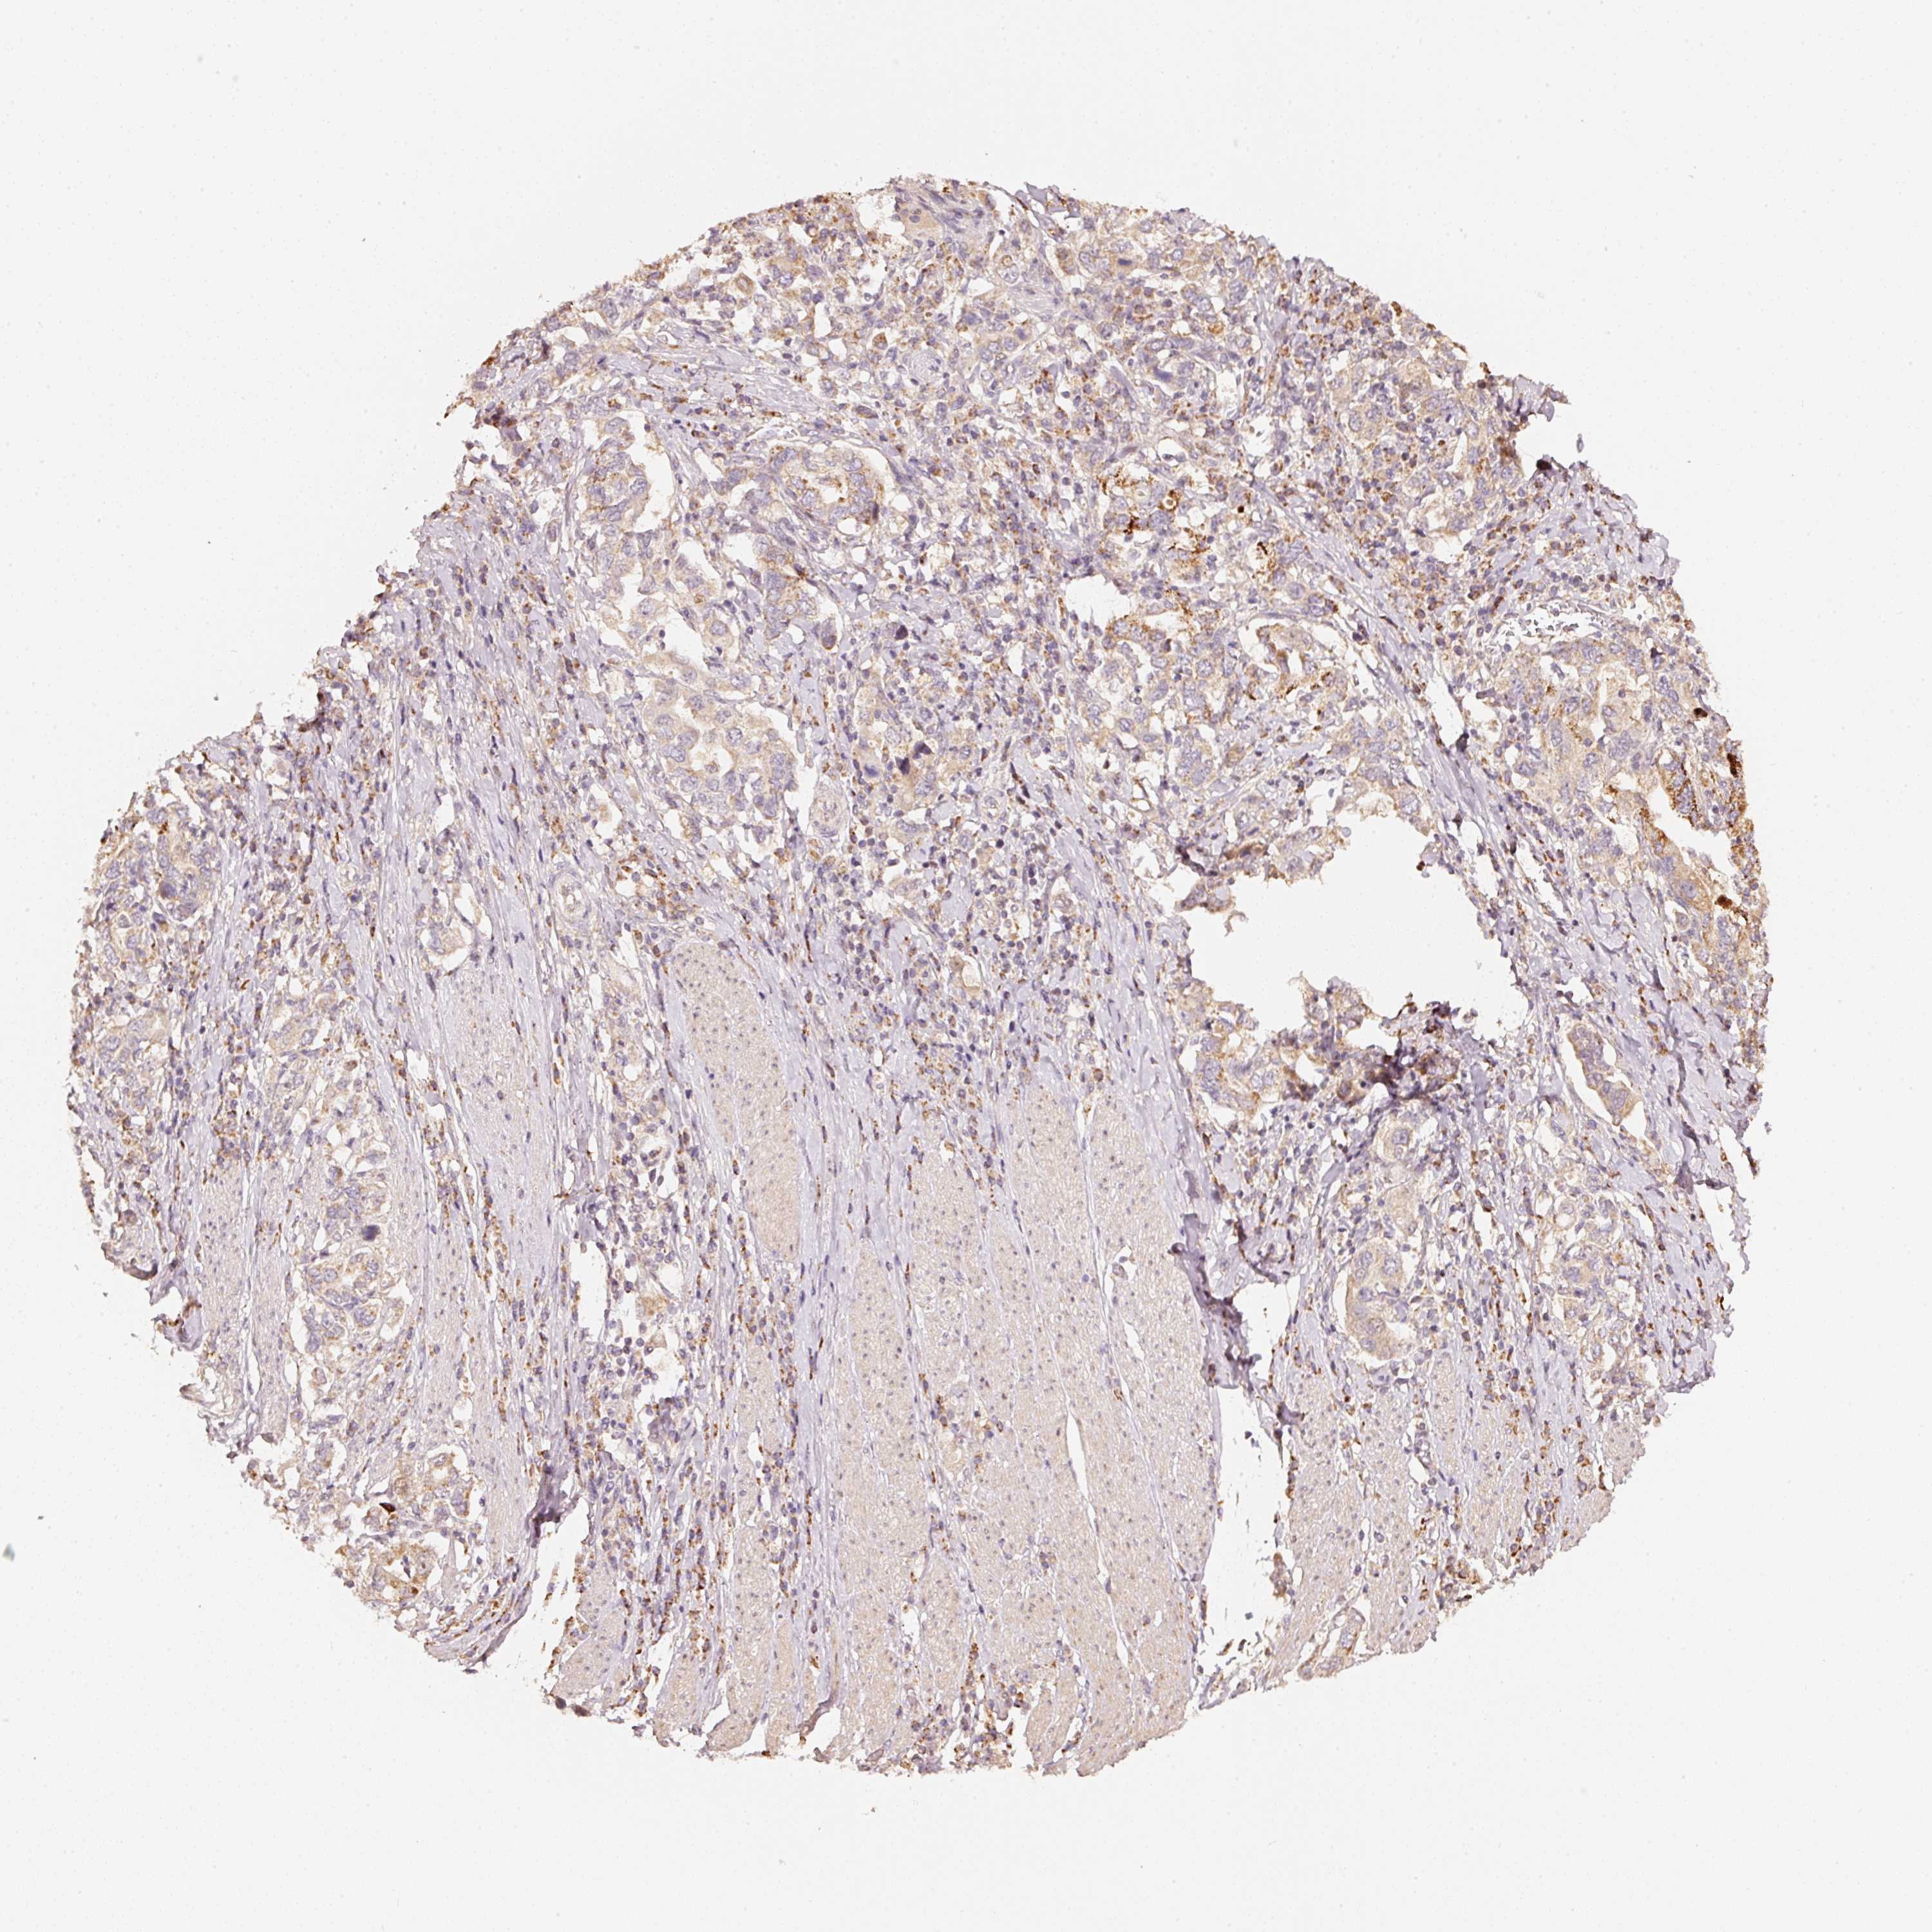

STOMACH CANCER - Protein expressioni

A mouse-over function shows sample information and annotation data. Click on an image to view it in a full screen mode. Samples can be filtered based on level of antibody staining by selecting one or several of the following categories: high, medium, low and not detected. The assay and annotation is described here.

Note that samples used for immunohistochemistry by the Human Protein Atlas do not correspond to samples in the TCGA dataset.

Antibody stainingi

Antibody staining in the annotated cell types in the current human tissue is reported as not detected, low, medium, or high, based on conventional immunohistochemistry profiling in selected tissues. This score is based on the combination of the staining intensity and fraction of stained cells.

Each image is clickable and will lead to virtual microscopy that enables deeper exploration of all samples and also displays staining intensity scores, fraction scores and subcellular localization as well as patient and tissue information for each sample.

Antibody HPA054146

Staining

High

Medium

Low

Not detected

Intensity

Strong

Moderate

Weak

Negative

Quantity

>75%

75%-25%

<25%

None

Location

Nuclear

Cytoplasmic/membranous

Cytoplasmic/membranous,nuclear

Adenocarcinoma, NOS